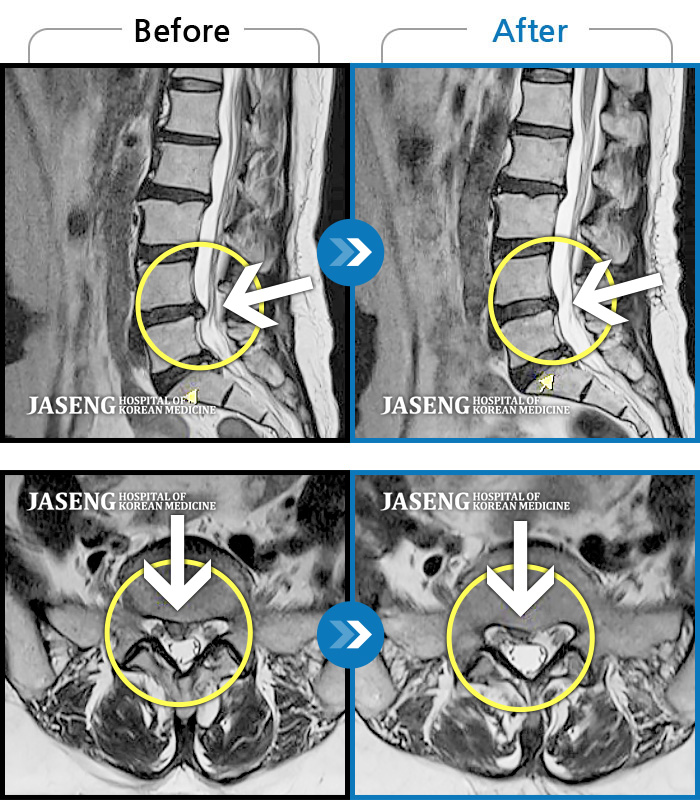

허리디스크

광주 · 김동은 원장

허리 통증과 양측 둔부부터 허벅지, 발목 부위 저리는 증상으로 내원하셨습니다.

촬영시기

2025.05.09 ~ 2025.12.18

2025.12.22